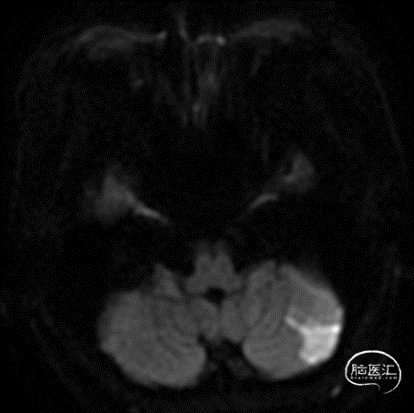

术前MRA未见颅内后循环及基底动脉显影,左侧小脑梗死。

患者术后苏醒麻醉,神志清,言语清晰,对答切题,四肢肌力同术前。术后即刻CT如下: